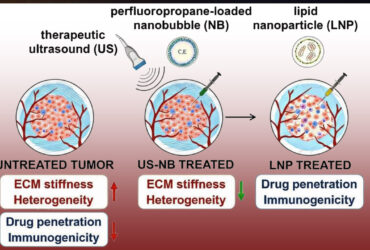

فروپاشی دژ نامرئی سرطان با فناوری نانوحباب

دانشمندان روشی یافتهاند که با نانوحباب و امواج فراصوت، سد سخت اطراف تومورها را نرم میکند. این کار باعث میشود داروها و سلولهای ایمنی راحتتر وارد بافت سرطانی شوند. این فناوری تازه میتواند طی دو سال آینده وارد مرحله آزمایش انسانی شود. هرچند فناوری نانوحباب توسعهیافته در آزمایشگاه اگزنر، هماکنون توسط شرکت ویسانو ترانواستیکس برای تشخیص سرطان پروستات استفاده میشود.